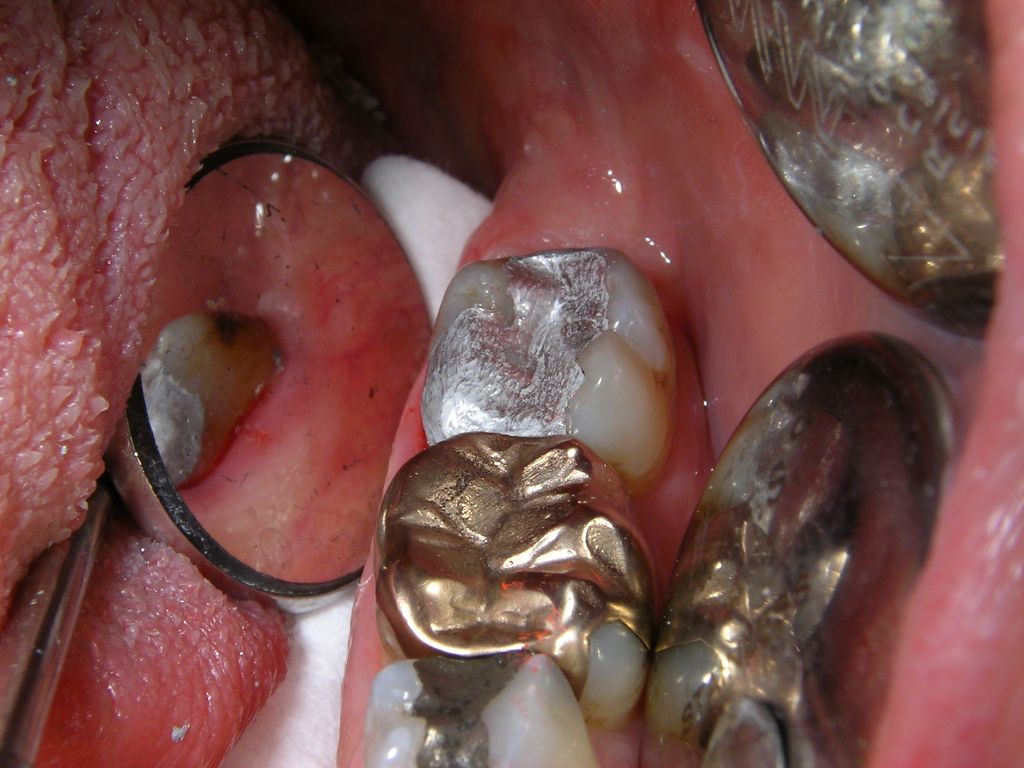

Mittelgroße und große Amalgamfüllung

Warum heute noch Amalgam? Weil die im Preis vergleichbaren (Zuzahlung bei mir je nach Größe ca. 30, 40, 55 oder 68 €), weißen Kunststofffüllungen (Komposit) trotz neuesten Materials und aufwendiger Verarbeitung die Haltbarkeit und Sicherheit von Amalgam noch nicht erreichen, wie umfangreiche Literaturübersichten gezeigt haben (1, 2, 3). Das gilt für den besonders kaubelasteten Seitenzahnbereich. Hier kommt es bei tiefen Kunststofffüllungen auch 4mal häufiger zum Absterben des Zahnnerven als mit Amalgam.